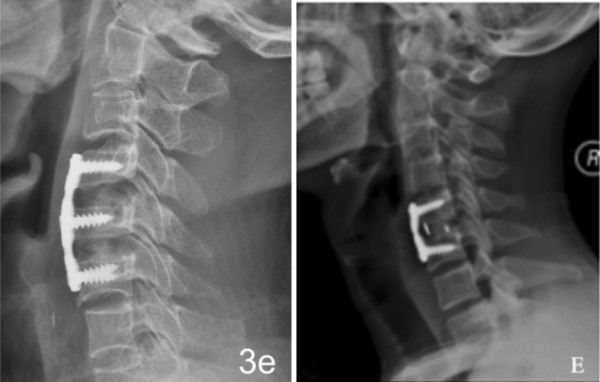

1.优异的生物相容性和生物活性

2.力学性能与自体骨匹配

3.弹性模量接近自体骨,有效减少应力遮挡

4.符合上下终版的解剖学特点